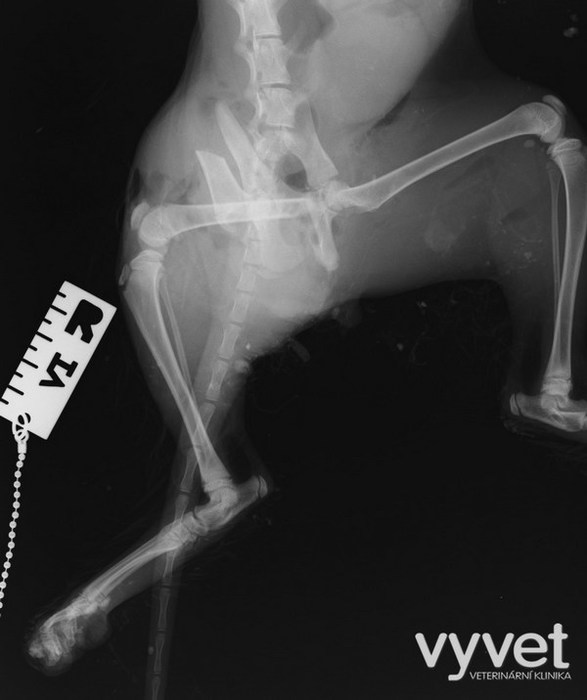

Nejčastějším problémem dlouhých kostí jsou zlomeniny (fraktury)

Rozdělujeme je do několika skupin podle charakteru, množství fragmentů, průběhu linie lomu, dislokace, stability atd.

Je mnoho popsaných metod fixací fraktur. Neinvazivní metodou je přikládání fixačních obvazů a kastů. Tento typ fixace však není ideální, protože nejsme schopni u zvířat zabezpečit dostatečně dlouhou dobu klidu pro srůst kosti. Ideální metodou je invazivnější přístup a to chirurgická repozice s následnou fixací osteosyntetickým materiálem.

Na našem pracovišti používáme zejména ploténky a hřeby.